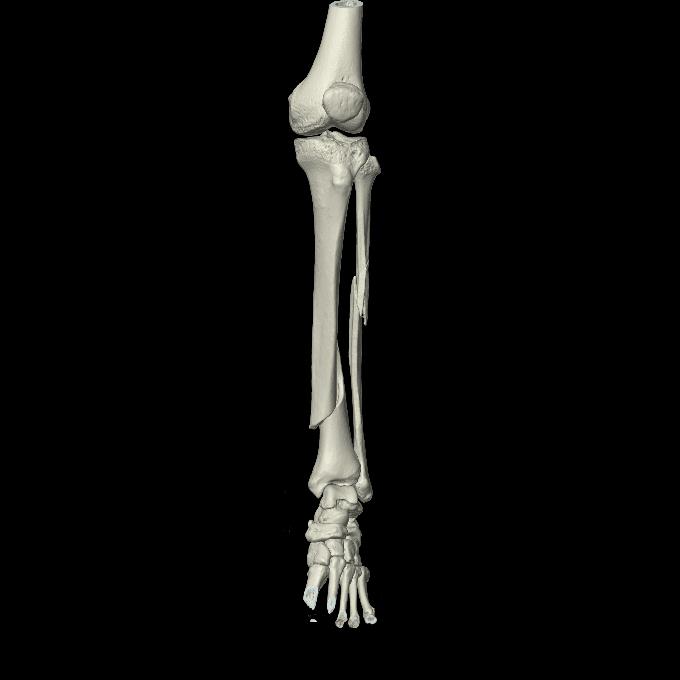

91983 11/16 左膝 2R 11/18 2R 55歳男性 脛骨骨切り術

102803 1/12(キウスなし) 1/27 左下腿 4R 30歳女性 左脛骨軸内釘

102755 1/4 2R 1/15 2R 右足関節 68歳女性 右三果脱臼骨折

110211 1/6 1/8 左前腕 4R 15歳男性 橈骨骨幹部骨折

103177 3/11 右足 2R 3/16 右足 2R リスフラン脱臼 55歳男性